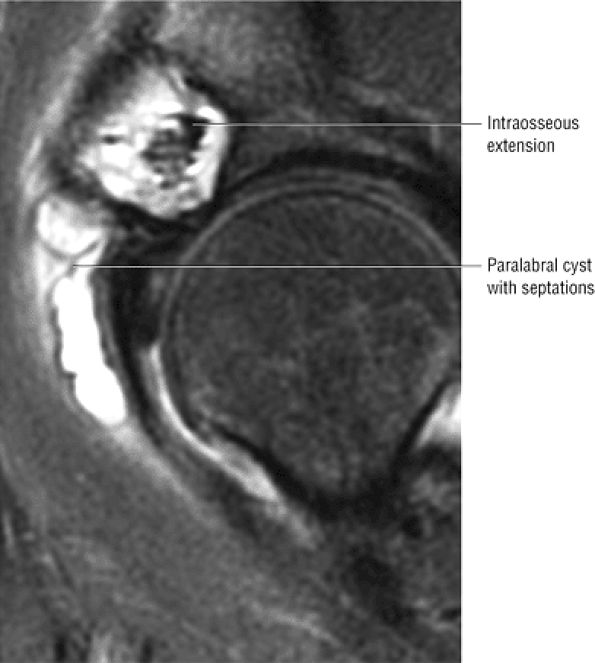

FIGURE 3.29 ● Normal axial anatomy of the hip. (A, B) At this level, the sciatic nerve can be seen exiting the sciatic foramen, deep to the piriformis muscle. Asymmetric enlargement of the piriformis muscle or masses in this region can cause impingement of the sciatic nerve, the so-called piriformis syndrome. (C, D) At this level the transition from the acetabular roof to the top of the femoral head is visualized. The thin arc of dark signal along the lateral margin of the acetabular roof represents the superior margin of the labrum. High signal in the superior labrum can be identified as a labral tear, and accompanying paralabral cysts are commonly identified extending superficial to the labrum. (E, F) The anterior labrum and the posterior labrum on axial images are identified as dark-signal triangles at the lateral margin of the acetabuli. Labral tears present as linear or irregular fluid signal extending through the substance of the labrum, or as expansion of the labrum by fluid signal extending to the surface of the labrum. Fluid signal interposed between the labrum and the acetabulum at the labral attachment indicates labral detachment.(G, H) Tendinosis of the gluteus medius and minimus insertions on the greater trochanter is visualized as thickening and increased signal of the tendons. Trochanteric bursitis can be identified either superficial or deep to the gluteus medius and minimus insertions. (I, J) A fluid collection anteromedial or anterolateral (or both) to the iliopsoas tendon is compatible with iliopsoas bursitis. Occasionally, iliopsoas bursitis may be present adjacent to an anterior labral tear, in which case it may be difficult to distinguish from a paralabral cyst. (K, L) The common hamstring origin on the ischium comprises the biceps femoris and semitendinosus tendons. The common hamstring tendon is a frequent site for tendinosis or partial tears, and the pathology is commonly symmetric.